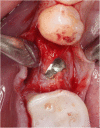

Methods: After randomization, 31 fully threaded titanium implants were inserted in 31 patients (16 men and 15 women) in the lower mandible using a split-flap technique. In the test group (10 patients), mucosa was treated with a PRF membrane. In the control group (21 patients), implantation was realized without soft tissue augmentation. Tissue thickness was measured at point of implant insertion (baseline) and at time of reentry after 3 months. Standardized digital radiographs were obtained for evaluation at time of implant placement, reentry after 3 months and at a 6-month follow-up. Data was analyzed by an independent examiner.